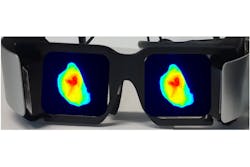

Suman Mondal is an instructor in the Radiology Department at WUSTL, part of the team also developing LS301. Mondal is designing imaging hardware to support FGS with near-IR fluorophores. In addition to imaging performance, their group is prioritizing two other requirements: minimizing impact in crowded operating rooms, and presenting a natural view to the surgeon. They’re addressing both those requirements with an augmented-reality head-mounted display they call the Goggle Augmented Imaging and Navigation System (GAINS).3

GAINS incorporates a near-IR illumination LED, a CMOS sensor, optical filters, head-mounted displays, and the image processing program to acquire and merge broadband and fluorescence images (see Fig. 4). They’ve been able to leverage advances in other applications. For example, Mondal says, “surveillance cameras have pushed near-IR sensor development from a quantum efficiency of 25% to 60% in just a few years.” GAINS has already demonstrated the ability to accurately visualize tumor margins in breast cancer, providing early validation of the technology. Mondal is working closely with clinicians, so their design iterations are driven by surgeons’ feedback. “About 30,000 women a year in the U.S. need repeat surgery because of incomplete resection,” he said. “Being part of a solution that will reduce the burden on the healthcare system is a big motivation for our work.”Shining a light on future developments